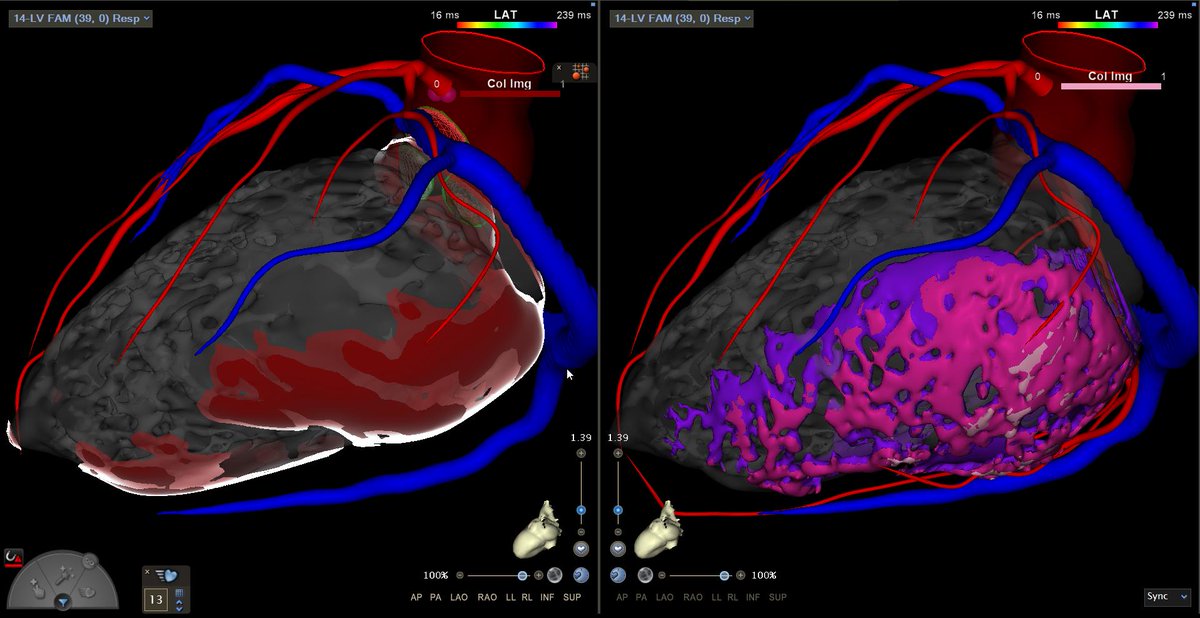

Congratulations to Dr. Demetrio Castillo, MD and Dr. Fergie J. Losiniecki, MD on a successful redo VT ablation! By comparing the #inHEART 3D model with the prior electroanatomical map, target areas were identified with greater precision and efficiency. We're happy to have

Challenging VT storm with multiple morphologies in a hemodynamically unstable patient for redo procedure. Substrate-guided strategy, focusing on areas of wavefront discontinuity with dual pacing wavefronts suggested a potential VT isthmus. Area corresponded nicely with